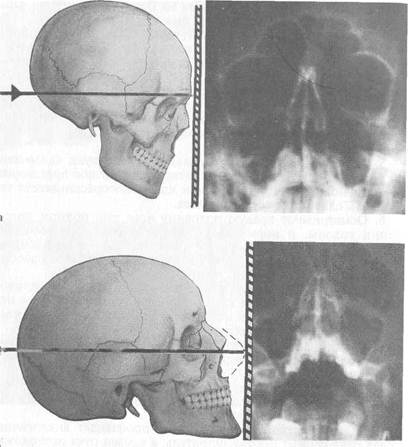

Рис. 1.4. Наиболее распространенные рентгенологические укладки используемые при исследовании околоносовых пазух.

а - носолобная (затылочно-лобная); б - носоподбородочная (затылочно-под-бородочная).

Рис. 1.4. Продолжение.

в — боковая (битемпоральная, профильная); г — аксиальная (подбородочно-вертикальная).

При носолобной проекции (затылочно-лобная) голову больного укладывают так, чтобы лоб и кончик носа лежалнна кассете. На полученном снимке лучше всего видны лобныей^в меньшей мере решетчатые и верхнечелюстные пазухи (рис. 1.4, а).

При носоподбородочной проекции (затылочно-подбородочная) больной лежит на кассете с открытым ртом, прикасаясь губами и подбородком к кассете. На таком снимке хорошо видны лобные пазухи, а также верхнечелюстные пазухи и ячейки решетчатого лабиринта (рис. 1.4, б).

При боковой (битемпоральная), или профильной, проекции голову обследуемого укладывают на кассете так, чтобы сагиттальная плоскость головы была параллельна кассете, рентгеновский луч проходит во фронтальном направлении чуть спереди от козелка ушной раковины на 1,5 см. На таком снимке бывают отчетливо видны лобные, клиновидные и в меньшей мере решетчатые пазухи в боковом их изображении. Однако в этой проекции пазухи с обеих сторон накладываются друг на друга, и можно судить об их глубине, но диагностика поражений правой или левой околоносовых пазух невозможна (рис. 1.4, в).

При аксиальной (подбородочно-вертикальная) проекции больной лежит на спине, откидывает голову назад и теменной частью укладывается на кассету. При этом положении подбородочная область находится в горизонтальном положении, а рентгеновский луч направляется строго вертикально на верхнюю щитовидную вырезку. При этой укладке хорошо дифференцируются клиновидные пазухи (рис. 1.4, г).